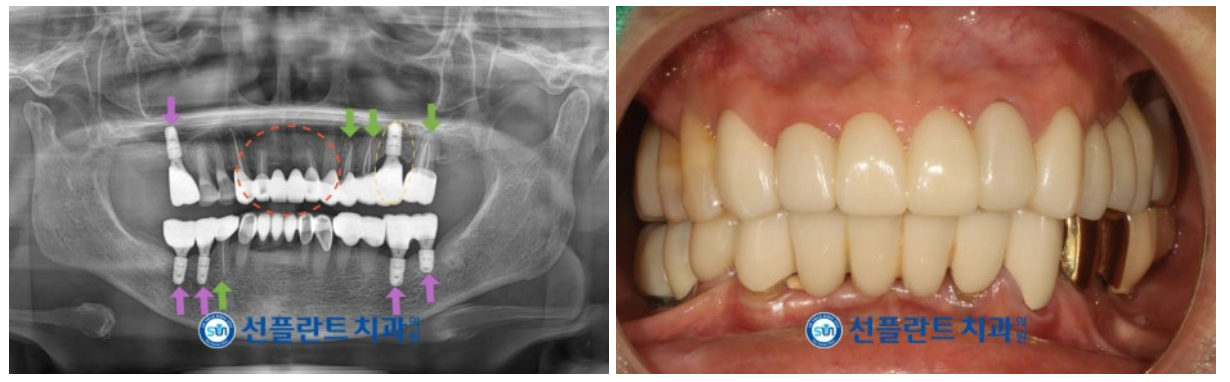

위턱 왼쪽 첫 번째 큰 어금니(#26)의

발치 후 충분한 시간이 지났을 때

임플란트 식립을 위해

잔존 치조골의 양과 두께, 상악동과의 거리,

눈에 보이지 않는 해부학적인 구조물 등을

면밀하게 파악한 뒤

뼈이식을 동반하여

임플란트 식립을 도와드렸습니다.

이 외에도

임플란트 식립이 필요한 부위에

정확한 방향으로 식립을 도와드렸으며,

임플란트와 잇몸뼈가

단단히 결합되기를 기다리는 동안

치아가 마모된 부위의

레진 치료도 진행해 드렸습니다.

임플란트 식립 후 충분한 시간이 지났을 때

단단히 결합되었는지

수치로 안정적인 것을 확인한 뒤

임플란트 최종 보철물 제작을 위한

인상채득을 진행하였으며,

최종 보철물은

추후 저작에도 무리 없게

완성도 높게 마무리해 드렸습니다.

모든 치료가 마무리된

구강 내 사진과 파노라마 사진인데요.

환자분께서는

어금니의 임플란트 식립을 통해

양측 저작이 편안해져서 만족해하셨으며,

앞니 보철물 교체로

심미성 회복을 통해

치과에 긍정적인 이미지를 갖게 되셨다고

말씀해 주셨는데요.